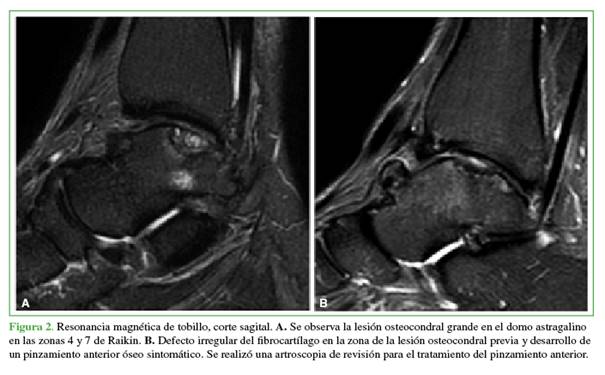

Un solo paciente requirió un nuevo procedimiento durante los 2 años de seguimiento, a causa del dolor provocado por un pinzamiento anterior desarrollado 18 meses después de la primera cirugía. Fue sometido a una nueva artroscopia anterior de tobillo para tratar el pinzamiento anterior y la resección de un cuerpo libre intrarticular (Figura 2).